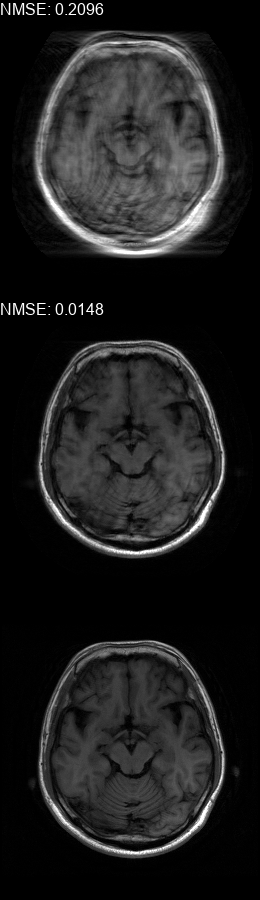

Fig. 5 contains four scan reconstructions from two patient cases. In both cases, the patient was requested to move at a certain time. In order to provide a ground truth for this scenario, another scan was performed using the same protocol for each patient, where the patient was required to hold still. The motion timing information for this case was obtained using the method described in [2] as it requires no additional hardware or changes to the scan protocol. We compare the reconstruction error using the SSIM [17] and the Visual Information Fidelity (VIF) [16] metrics, since a pixelwise comparison is not viable in this case.

Figure 5: Examples of real motion corrupted images together with their motion corrected counterparts. The bottom row shows a corresponding slice from a motion-free acquisition of the same subject. These motion-free images were acquired using an additional scan. The images on the top row are motion-corrupted. Images on the middle row were corrected using our method. (a,b) motion was was detected at t1=96subscript𝑡196t_{1}\!=\!96, (c,d) the motion was detected at t1=112subscript𝑡1112t_{1}\!=\!112. All scans were acquired using 𝒮260subscript𝒮260\mathcal{FS}_{260} presented in Fig. 1b.